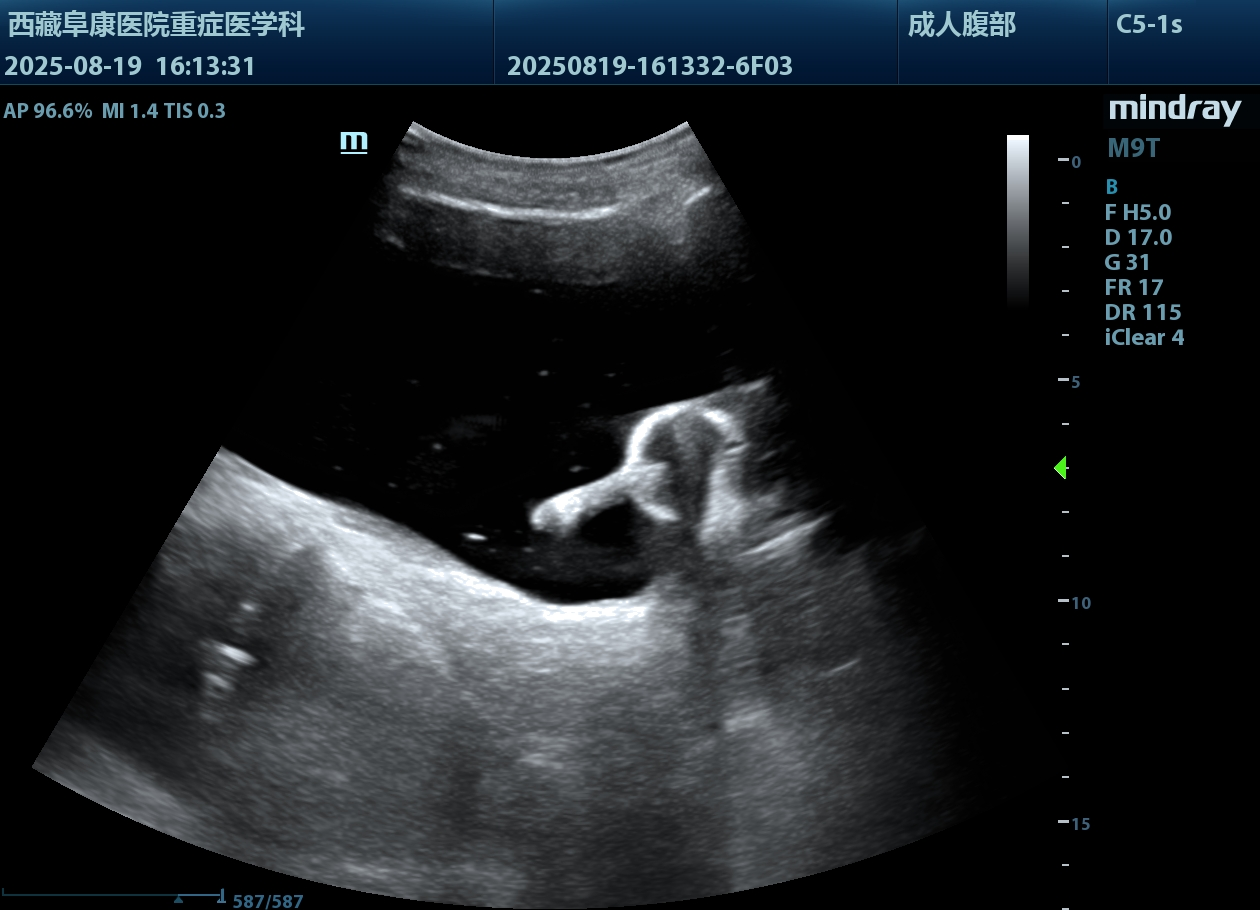

由于情況緊急,醫(yī)護人員沒有半分遲疑,除了導(dǎo)尿所需的物品,考慮到老人年紀大了,必須先確認情況,半點馬虎不得,他們特意帶上B超機,拎起出診箱,火速趕往老人家中。

推開門,只見老人蜷縮在藏式床上,身子微微發(fā)顫。醫(yī)護人員放輕腳步,俯身輕聲安撫:“大爺,我們先幫您看看情況,不難受的?!毕仁禽p柔查體,感知膨隆小腹下的膀胱充盈度;再用B超機細致探查,醫(yī)護人員邊操作邊低聲講解流程。慢慢地老人緊繃的身體放松下來,默許了檢查??墒翘岬綄?dǎo)尿時,還是擺著手抗拒。醫(yī)護人員和家屬耐著性子反復(fù)勸說,許久后,他終于輕輕點了頭。